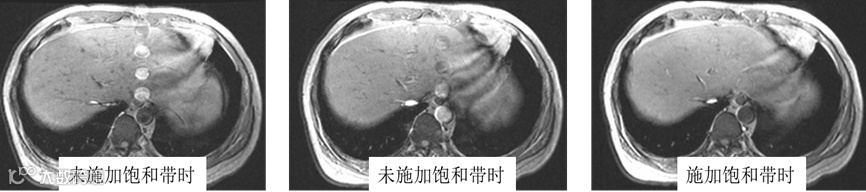

周期运动伪影与门控技术:有些运动如呼吸运动、心脏收缩舒张以及大血管的搏动虽然是不自主的但它们具有周期性,属于周期性的循环往复的运动。对于周期性运动可以采用呼吸门控或者心电门控来实现数据采集的同步化。所谓数据采集的同步化简单的理解就是在绝对运动中通过门控来寻找相对的静止,这样在不同运动周期中的相同时刻采集相同的K空间数据,这样就等同于冻结了运动。呼吸门控和心电门控是解决呼吸运动和心脏运动的非常有效的成像方式,不过如果成像过程中如果呼吸频率或者心跳频率等频繁发生改变,这样虽然在理论上相同的时刻采集的K空间数据,但此时的K空间数据采集时物体却处于不同的空间位置,这就会导致图像中产生明显的Ghost鬼影,鬼影简单的理解就是同一个解剖结构表现为图像中一系列相互复制的重影。当采用门控技术时成像的TR时间就由周期性运动的周期及门控参数设置中选择的RR间期数来决定。对于呼吸门控而言,显然不能利用呼吸门控方式的来直接采集T1加权图像,如基于FSE序列的T1加权像就不能采用呼吸门控的采集方式。以往会通过呼吸补偿方式来减少呼吸导致的运动伪影,也就是数据采集不是通过门控触发来控制,但在成像过程中记录门控相关信号,这样在图像重建过程中根据门控相关信号重新排布K空间数据。呼吸补偿总体效果不是很理想,根据成像过程中采用的激励次数又分为高阶补偿和低阶补偿两种模式,不同的补偿模式对于K空间数据进行不同的排布方式,从而改变鬼影的空间分布。理论上采用更多的激励次数时可以把鬼影的间距拉大,这样就可以在重建的图像中看不到该鬼影,但需要更长的扫描时间。呼吸或心动补偿技术现在基本很少使用了。迄今在进行3D LAVA等成像时施加的呼吸门控或者导航波方式是利用门控或者导航信号作为触发信号,每次触发后会进行一系列的射频激励,所以TR时间并不是由门控信号直接决定的,这个需要和用于T2加权像的呼吸门控有所区分。

图3说明:肝脏等腹部成像过程中采用门控技术可以明显改善呼吸导致的运动伪影。